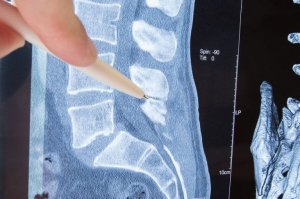

脊柱または脊椎は、椎骨によって形成され、骨を保護し、体が自由に動くことを可能にします。椎骨には両側に穴があり、体のさまざまな部分に繋がる神経が出ています。

椎骨から出る神経は「神経根」と呼ばれます。神経根障害は、その神経根で起こる神経圧迫です。では、その原因は? 症状はどんなものが? 今回の記事では、これらの質問に答え、既存の治療法についてもご紹介します。